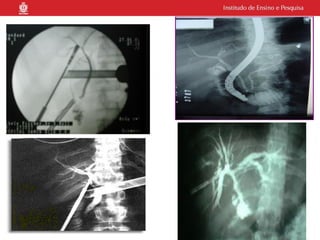

O documento descreve indicações para exames de imagem de ductos biliares, incluindo colangiografia retrógrada endoscópica para pacientes com cálculos migrados da vesícula biliar ou pacientes ictéricos. Ele também menciona radiografia piloto, uso de contraste hidrossolúvel e que o procedimento é realizado por um médico gastroendoscopista.